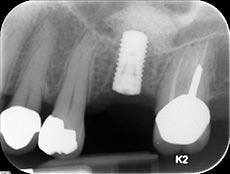

1. Levin L and Halperin-Sternfeld M. Tooth preservation or implant placement: A systematic review of long-term tooth and implant survival rates. The Journal of the American Dental Association. October 1, 2013 vol. 144 no. 10 1119-1133.